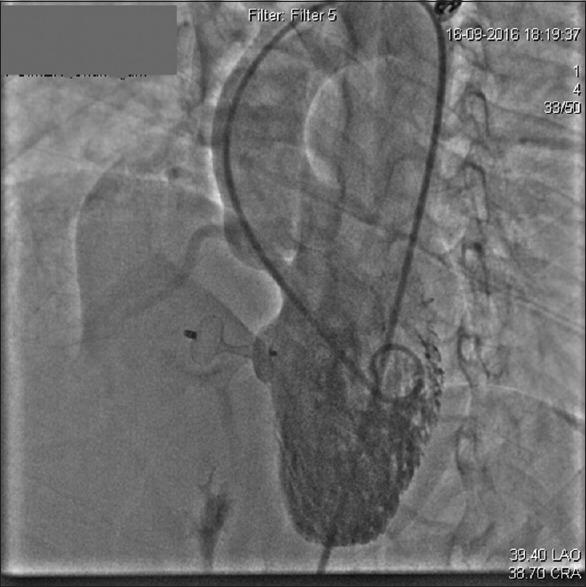

Asymmetrical septal occluder device (ASOD) has made percutaneous closure of ventricular septal defect an easy and effective management option. Although there are reports of aortic and tricuspid valvular regurgitation after deployment of ASOD, only few cases of tricuspid stenosis (TS) has been reported so far in the literature. We report a case of malaligned ASOD that occurred after successful device closure resulting in TS along with mild tricuspid and aortic regurgitation requiring surgical retrieval. Transesophageal echocardiography played crucial role in detecting the cause of tricuspid valve dysfunction besides providing continuous monitoring during the procedure. We intend to emphasize the need of echocardiographic evaluation of the tricuspid valvular apparatus and aortic valve during and after the device deployment even after the successful device closure to prevent this rare complication.

摘要

不对称性室间隔封堵器(ASOD)使经皮闭合室间隔缺损成为一种简便有效的治疗选择。尽管有报道称ASOD植入后出现主动脉瓣和三尖瓣反流,但迄今为止,文献中仅报道了少数三尖瓣狭窄(TS)病例。我们报告一例在成功进行封堵器闭合术后发生的ASOD位置不当病例,导致TS以及轻度三尖瓣和主动脉瓣反流,需要通过手术取出封堵器。经食管超声心动图除了在手术过程中提供持续监测外,在检测三尖瓣功能障碍的原因方面发挥了关键作用。我们旨在强调,即使封堵器成功闭合,在封堵器植入期间及之后,也需要对三尖瓣装置和主动脉瓣进行超声心动图评估,以预防这种罕见的并发症。